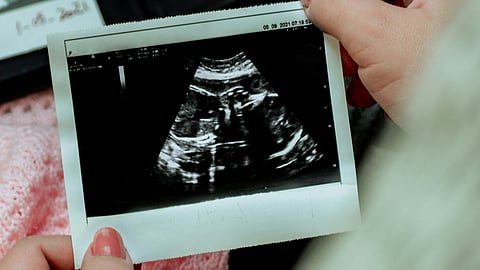

Most parents can think back to the first ultrasound image they saw of their unborn child, and may even be able to remember what impression that image had on them.

New research suggests these initial perceptions may have been formed, at least in part, in response to how the health care provider described the baby during the exam.

These prenatal care experiences play a large role in shaping how parents see their babies and, consequently, affect how parents relate to their children later on and how those children behave in return, according to new research from the University of Notre Dame.

The ultrasound experience is such a salient, emotional part of the pregnancy overall, legitimizing the pregnancy itself and creating an opportunity for brand-new memories with the baby.

“The words used in these conversations with ultrasound technicians or obstetric sonographers — whom we consider experts on fetal development — get absorbed and influence who you think your child is before they’re even born,” Kaylin Hill[1], assistant professor in Notre Dame’s Department of Psychology[2] and lead author of the study published in Communications Psychology[3], a Nature journal.